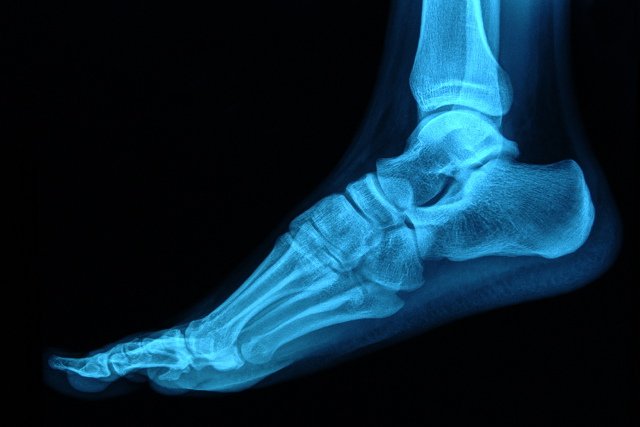

Stopa to niezwykła konstrukcja, która składają się z wielu niewielkich kości, powiązanych ze sobą więzadłami, podtrzymywanych przez wiele grup mięśniowych. Stanowi ona nasza podstawę, przenosi cały ciężar ciała i dostosowuje się jednocześnie do podłoża, po którym się poruszamy. Stopa ma również potencjał, jeśli chodzi o magazynowanie energii. Jest to szczególnie ważne przy dynamicznym poruszaniu się. Według badaczy ewolucji, pojawienie się charakterystycznego wyłącznie dla człowieka łuku było wymuszone przez... bieganie!

Do efektywnego działania stopa potrzebuje zarówno małych mięśni, które wraz z więzadłami i masywnym rozcięgnem stabilizują łuki, jak i dużych długich mięśni zaczynających się na podudziu (o wiele większym przekroju), które poruszają całością, choć też biorą udział w podtrzymaniu wysklepień stopy. Z każdym krokiem cztery warstwy drobnych mięśni kontrolują stopień i prędkość odkształcania się łuków. Jeśli nie działają właściwie nasza „baza” przestaje być stabilna, a w następstwie dochodzi do niekontrolowanego ruchu i nadmiernego odkształcania łuku. Do niedawna krótkie mięśnie stopy nie były brane pod uwagę w leczeniu kontuzji przeciążeniowych takich jak zapalenie rozcięgna podeszwowego, czy zespół mięśnia piszczelowego tylnego.

W świecie zwierząt jesteśmy jedynymi dwunożnymi biegaczami. Pozwalają na to dobrze rozwinięte struktury takie jak ścięgno Achillesa i rozcięgno podeszwowe, które są słabo rozwinięte np. u małp. W przeciwieństwie do czworonogów, mamy również aktywne mięśnie krótkie stopy, które u nich zanikły prawie zupełnie. Są one (wraz z mięśniami zaopatrującymi staw skokowy) niezbędne, aby stopa dostosowała się do podłoża z jednoczesnym utrzymaniem równowagi całego ciała. Aktywne utrzymanie równowagi przy tak niewielkiej płaszczyźnie podparcia to prawdziwy majstersztyk inżynierii (naukowcom udało się już zrobić całkiem dobrze utrzymującego równowagę czworonożnego robota – na dwunożnego, o zdolnościach zbliżonych do ludzkich, na razie czekamy).

Jak w takim razie uzyskujemy tak niezwykłą równowagę przy jednoczesnej dynamice? Naukowcy podzielili system na trzy części: bierną (ustawienie kości względem siebie, więzadła, rozcięgno itp.), aktywną (mięśnie) i kontrolująca (receptory mięśni, ścięgien, powięzi czy podeszwy). O ile na pierwszą część nie mamy wpływu (chyba, że ktoś z Państwa jest chirurgiem), o tyle reszta tego systemu, jak cały narząd ruchu podlega treningowi. Jak dotąd najmniej uwagi zwracano na krótkie mięśnie stopy. Nie generują one dużych sił, więc nie wydają się specjalnie istotne dla treningu biegowego.

Cztery warstwy mięśni znajdujących się pod stopą, jak pokazują badania przy użyciu EMG, mają istotny wpływ na ustawienie łuków stopy w fazie podporu (dużo większa niż np. podczas chodu). Tym samym wpływają one na obciążenie innych struktur podtrzymujących wysklepienie np. rozcięgna podeszwowego. Ponieważ nasze stopy codziennie zamknięte są w obuwiu, krótkie mięśnie stopy nie mają specjalnie okazji być aktywne. Aby sprawdzić jak pracują i czy mamy świadomą nad nimi kontrolę proponuje spróbować paru prostych ćwiczeń. Dla osób pokonujących co tydzień wiele kilometrów podczas treningów to właściwie pozycja obowiązkowa.